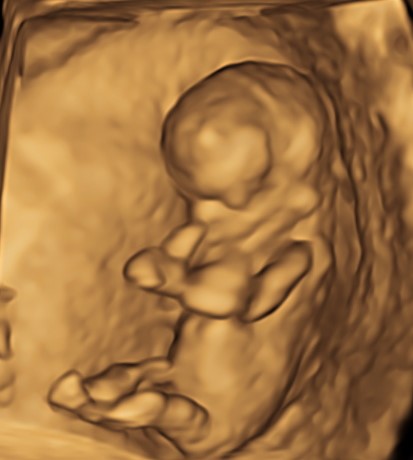

Indipendentemente dalla nostra scelta, è di capitale importanza fare comunque una ecografia fra la 11° e la 13° settimana. Infatti già a questa epoca gestazionale siamo in grado di condurre un’iniziale valutazione morfologica. Ma soprattutto questo è la finestra di opportunità per studiare la translucenza nucale. In realtà questa ampia finestra di tre settimane ha il suo momento più favorevole a 11 settimane e mezza e inizio dodicesima.

Si va a misurare quindi attraverso una ecografia lo spazio dietro la nuca: è una fisiologica raccolta di linfa che tende ad aumentare in diverse situazioni patologiche risultando essere un indice generale di buon andamento della gravidanza dove più è sottile più siamo tranquilli a riguardo di patologie cromosomiche, malformazioni cardiache, ed alcune malattie genetiche.

In questi 4/5 centimetri la risoluzione degli apparecchi moderni riesce a fare una prima valutazione morfologica, per vedere che ci siano tutti i “necessori” ed eventualmente anche accessori: cercando è possibile evidenziare il tubercolo genitale (sempre che il piccolo decida di essere collaborante e mostrare le proprie grazie). Si chiama così perché clitoride e pisellino hanno le stesse dimensioni a questa epoca, ma è possibile riconoscerli in base all’angolo rispetto al corpo: parallelo al corpo per le signorine, verso l’alto per i maschietti. Attenzione però la sensibilità, ovvero quanto ci azzecchiamo, è intorno al 60%.

La parte morfologica è molto importante, riusciamo a studiare l’estremo cefalico – a questa epoca il cervello fetale è molto semplice – , il massiccio facciale con occhi, naso bocca, le orecchie sono abbastanza facili da essere evidenziate. Nel torace oltre ai campi polmonari possiamo vedere il cuore battere ritmicamente e confermare la presenza delle quattro camere cardiache. Nell’addome riusciamo ad evidenziare lo stomaco e l’inserzione del cordone ombelicale. Si nota la presenza della vescica e del tubercolo genitale. Si possono esplorare tutti e quattro gli arti.

Per i genitori vedere sotto i propri occhi prendere forma il tesorino risulta una esperienza indimenticabile e impareggiabile al limite fra incredulità e la sorpresa come tutto sia già presente seppur in scala ridotta.